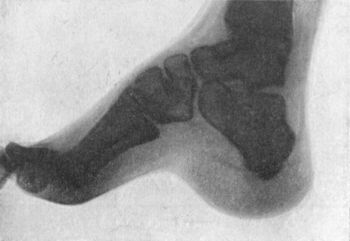

| 151. | Radiogram of Foot of Adult, showing Changes in the Bones in Pes Cavus | 286 |

| 150. | Pes Cavus in Association with Pes Equinus, the Result of Poliomyelitis | 286 |